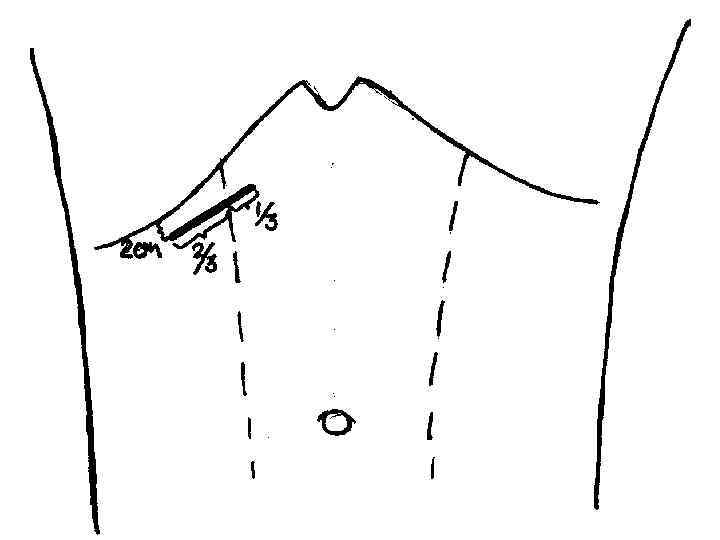

Кіші жолмен жасалатын холецистоэктомия Көрсеткіштері: - жедел калькулезді холецистит - холецистолитиаз, холедохолитиаз, кеңеймеген; -ЛХЭ кезіндегі техникалық қиыншылықтар. Қарсы көрсеткіштер: - іш қуысы ағзаларын интраоперационды ревизия жасау қажеттілігі; - Жайылған перитонит.

Вскрытие брюшины при ХЭ из МПД. Захват дна желчного пузыря окончатым зажимом. Субсерозное выделение желчного пузыря с помощью электрокоагуляции.